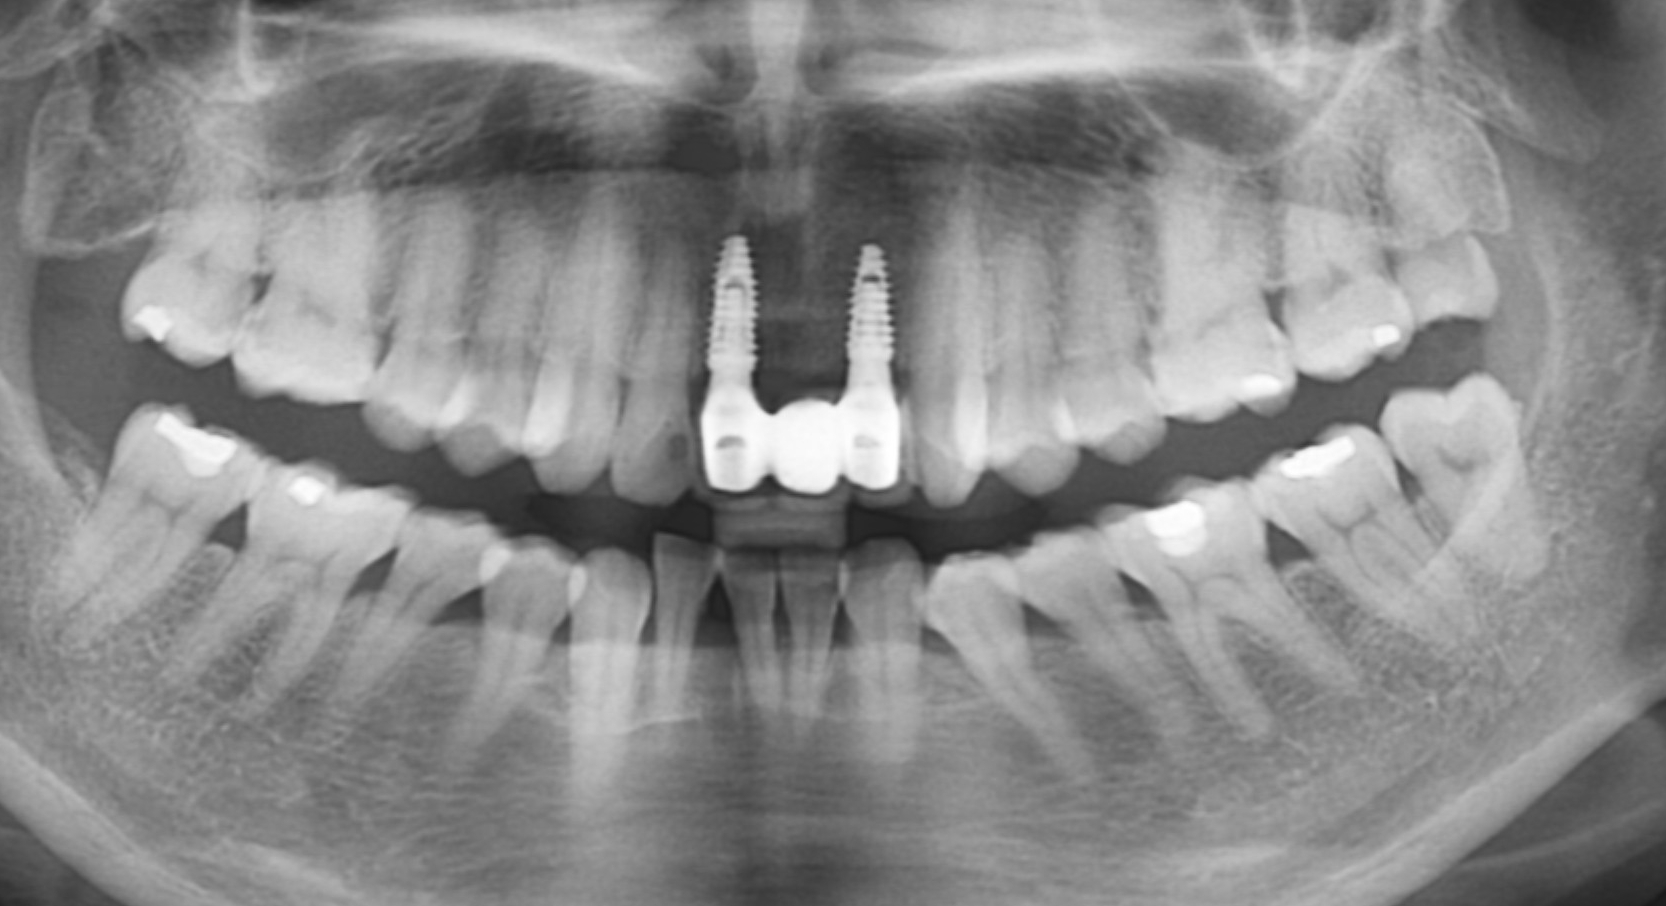

[임플란트] 제목 : 전치부 임플란트 브릿지

앞니의 임플란트입니다.